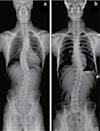

40 콜로라도 타임즈 · 2023년 4월 27일 목요일 · 1074호 교통사고 후유증 / 목 통증 / 목 디스크 / 오십견 / 어깨통증 말초신경장애: 손, 발, 다리의 통증, 저림, 근육약화감, 감각상실 (편)두통 / 불면증 / 어지러움 / 턱관절 장애(TMJ) 척추측만증(Scoliosis) / 척추협착증 / 허리수술 후유증 허리통증 / 허리 디스크 / 관절염 / 좌골신경통 / 고관절, 발목, 손목 통증 ▪ ▪ ▪ ▪ ▪ ▪ ▪ ▪ ▪ 최첨단 목/허리 디스트 치료기기 최신형 디지털 X-ray 시설 Therapeutic Massage ▪초음파, 전기치료 Gonstead Chiropractic 교정치료 치료 진료과목 교통사고 치료 전문 자동차 보험 건강 보험 상해 보험 Southern California University of Health Science Doctor of Chiropractic 콜로라도주 척추신경 보드 정회원 캘리포니아주 척추신경과 보드 정회원 National Board 척추신경과 정회원 손석기 D.C. 원장, 척추신경 전문의 chiro1health@gmail.com Open Hours 월/수/금 9am-6pm 화/목: 2pm-6pm 청소년을 위한 척추교정 프로그램 우버와 같은